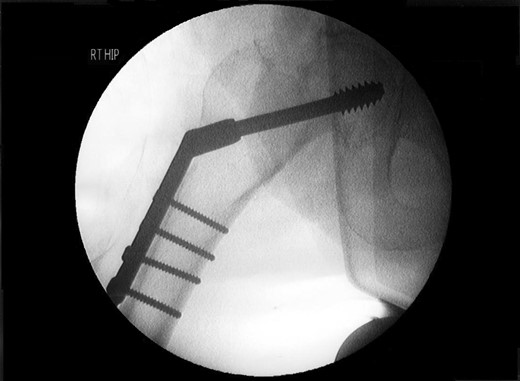

A lady of 88 years old presented with pain in her right hip following a fall at home. Radiographs of the proximal femur revealed an extra-capsular fracture, as shown in Fig. 1. She was taken to the operating theatre within 48 h. In an uncomplicated procedure, the fracture was fixed with a 75-mm, 135°, dynamic hip screw (DHS). A short (25-mm) barrel with four-hole plate was used. Intraoperative screening images are shown in Fig. 2. This position was accepted.

Review of the intraoperative radiographs (Fig. 2) shows that the barrel and screw are not properly engaged. Although the films may appear satisfactory at first glance, closer consideration reveals that the long axes of the barrel and screw are imperfectly aligned (Fig. 2). Following later experimentation on the bench with identical components, we discover that this is only possible when the length of overlap between barrel and screw is <3 mm. With such minimal overlap, the screw is resting on the lip of the barrel, yet is not fully engaged. In such a position, the screw cannot slide within the barrel. At overlaps greater than this, the screw and barrel cannot be other than coaxial.

Previous correspondents have explained the failure of the screw to slide within the barrel as a ratio of the length contained within the barrel, and the length protruding from it. In order to slide smoothly, without danger of binding, the length of screw protruding should be <4.7 times the length contained within the barrel [2]. This was not achieved here.

We hypothesize that the cause of failure was an intraoperative measurement error, leading to the selection and placement of a 75-mm screw, which was in fact of inadequate length. Thinking, however, that the selection was correct, the surgeon also chose to employ a short 25-mm DHS barrel following recommended practice from the literature [3]. This combination of components was too short to engage properly. Being improperly engaged, they were unable to slide as intended, and upon attempted mobilization by the patient, they immediately uncoupled the one from the other.

Intraoperative screening at the time of placement of the screw may concentrate on visualization of the proximal tip of the implant, to ensure that it occupies a satisfactory position in the femoral head and does not protrude into the hip joint. We stress that equal attention should be paid to the distal end, to ensure that it is correctly aligned with the barrel. Closer scrutiny of the intraoperative screening films for evidence of the appearance described above could have identified this avoidable complication, the resolution of which required major revision surgery.